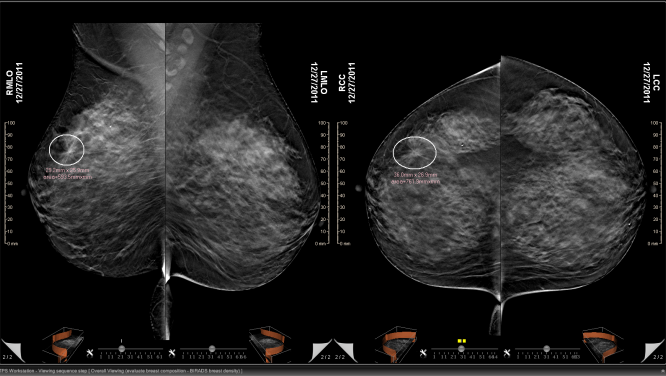

«Σε 99% ανέρχεται το ποσοστό ακρίβειας της ψηφιακής τομοσύνθεσης, της τελευταίας εξέλιξης στην ψηφιακή μαστογραφία, για την έγκαιρη διάγνωση...